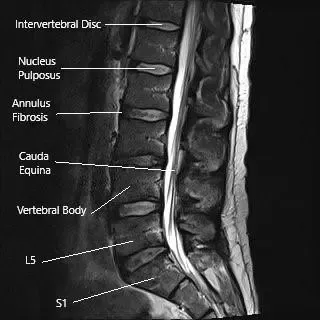

MRI of lumbar spine in sagittal section

- MRI: The gold standard for detecting spinal cord and nerve compression, showing both soft tissue and bone detail.

MRI is crucial for evaluating soft tissue structures, bone marrow involvement, and the relationship of the tumor to the spinal cord and nerves. It provides detailed information that helps in planning treatment.